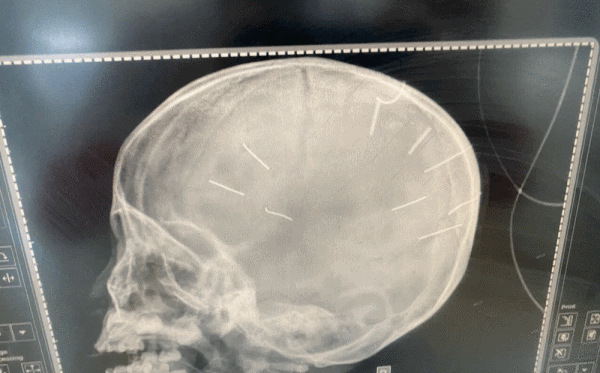

베트남이슈 베트남, 3세 여아의 두개골에서 이물질 9개 발견… 엄마의 남자 친구 수사 중

지난 1/7일 오후 하노이시 탁탓 종합병원에 혼수 상태로 입원한 47개월 여아를 검진하던 중 오른팔이 부러져 치료를 받은 상태와 함께 두개골에서 핀으로 의심되는 이물질 9개가 발견되어 지역 경찰에 신고해 아동학대 협의로 조사가 진행되고 있다고 지난 1/18일 해당 병원장과의 인터뷰에서 알려졌다고 zingnews가 전했다.

[사진 출처: D.X. / zingnews]

지금까지 조사 중 여아는 약 3개월 전 농약중독으로 혼수상태에 빠져 국립아동병원에서 치료를 받은 것으로 알려졌으며, 약 2개월 후 여아는 소화관 내 이물질로 병원에 다시 입원하는 등 지속적으로 병원을 방문했던 것으로 알려졌다.

현재 여아는 치료를 위해 시립 병원인 세인트폴 병원으로 이송된 상태지만 위독한 상태로 알려졌으며, 관련하여 현재 하노이시 경찰 당국은 추가적인 정보 제공을 거부한 상태다.

한편, 오늘까지 알려진 내용에 따르면 지역 경찰은 여아 어머니의 남자 친구를 용의자로 불러 수사 중인 것으로 알려졌다.